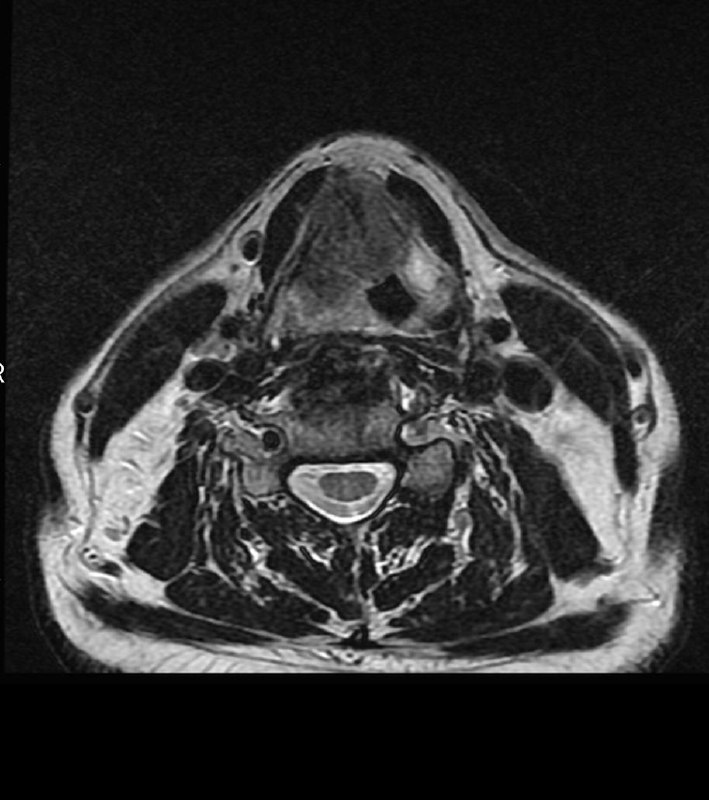

Больной 70 лет.

Выраженная осиплость голоса в течение полугода.

ЛОР-врачи ставят ларингит.

Делали биопсию: вот результат.

И какое здесь Т?